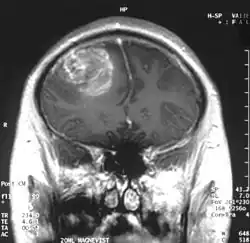

| A coronal view (from the back of the head) of a contrast-enhanced MRI revealing a glioblastoma in a 15-year-old boy | |

When viewed with MRI, glioblastomas often appear as ring-enhancing lesions. The appearance is not specific, however, as other lesions such as abscess, metastasis, tumefactive multiple sclerosis, and other entities may have a similar appearance.[61] Definitive diagnosis of a suspected GBM on CT or MRI requires a stereotactic biopsy or a craniotomy with tumor resection and pathologic confirmation. Because the tumor grade is based upon the most malignant portion of the tumor, biopsy or subtotal tumor resection can result in undergrading of the lesion. Imaging of tumor blood flow using perfusion MRI and measuring tumor metabolite concentration with MR spectroscopy may add diagnostic value to standard MRI in select cases by showing increased relative cerebral blood volume and increased choline peak, respectively, but pathology remains the gold standard for diagnosis and molecular characterization.